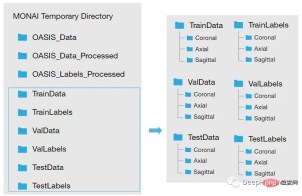

因为模型需要的是二维切片,所以将每个切片保存在不同的文件夹中,如下图所示。这两个代码单元将训练集的每个MRI体积的切片保存为“.png”格式。

<code>Save coronal slices for training images dir = root_dir + '/TrainData' os.makedirs(os.path.join(dir, "Coronal")) path = root_dir + '/TrainData/Coronal/' for file in sorted(glob(os.path.join(root_dir + '/TrainData', '*.nii'))): image=torchio.ScalarImage(file) data = image.data filename = os.path.basename(file) filename = os.path.splitext(filename) for i in range(0, 208): slice = data[0, :, i] array = slice.numpy() data_dir = root_dir + '/TrainData/Coronal/' + filename[0] + '_slice' + str(i) + '.png' plt.imsave(fname = data_dir, arr = array, format = 'png', cmap = plt.cm.gray)</code>

同理,下面是保存标签:

<code>dir = root_dir + '/TrainLabels' os.makedirs(os.path.join(dir, "Coronal")) path = root_dir + '/TrainLabels/Coronal/' for file in sorted(glob(os.path.join(root_dir + '/TrainLabels', '*.nii'))): label = torchio.LabelMap(file) data = label.data filename = os.path.basename(file) filename = os.path.splitext(filename) for i in range(0, 208): slice = data[0, :, i] array = slice.numpy() data_dir = root_dir + '/TrainLabels/Coronal/' + filename[0] + '_slice' + str(i) + '.png' plt.imsave(fname = data_dir, arr = array, format = 'png')</code>